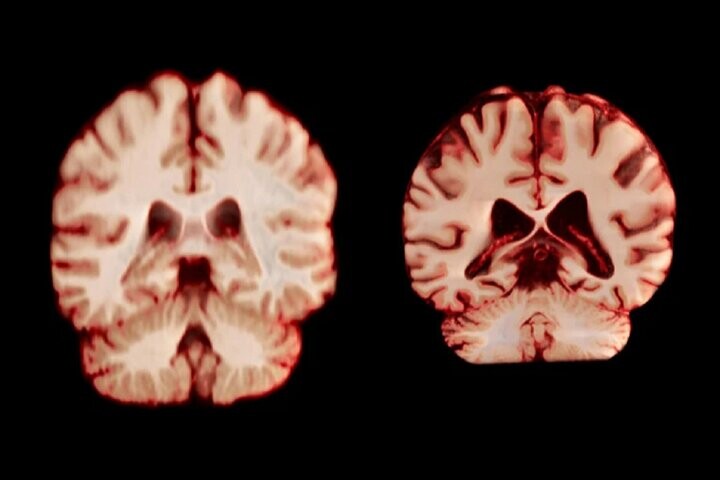

اسکن مغز

جدیدترین مطالعه شامل بیش از ۱۲ هزار و ۵۰۰ اسکن مغزی تصویربرداری تشدید مغناطیسی (MRI) از ۴۷۲۶ نفر بود که حداقل دو اسکن برای هر نفر، با فاصله متوسط ‌سه سال انجام شده بود که به بیماری آلزایمر یا هرگونه اختلال شناختی مبتلا نبودند و به عنوان شرکت‌کننده کنترل در ۱۴ مجموعه داده بزرگتر قرار داشتند. محققان با بررسی عواملی از جمله ضخامت ماده خاکستری و اندازه نواحی مرتبط با بیماری آلزایمر، مانند هیپوکامپ که برای حافظه ضروری است، نحوه تغییر ساختار مغز افراد را در طول زمان مقایسه کردند.

به طور کلی، مردان در مقایسه با زنان، کاهش حجم بیشتری را در مناطق بیشتری از مغز تجربه کردند. به عنوان مثال، قشر پس مرکزی که مسئول پردازش احساسات لامسه، درد و دما و همچنین موقعیت و حرکات بدن است، در مردان سالانه ۲.۰ درصد و در زنان سالانه ۱.۲ درصد کاهش یافت.